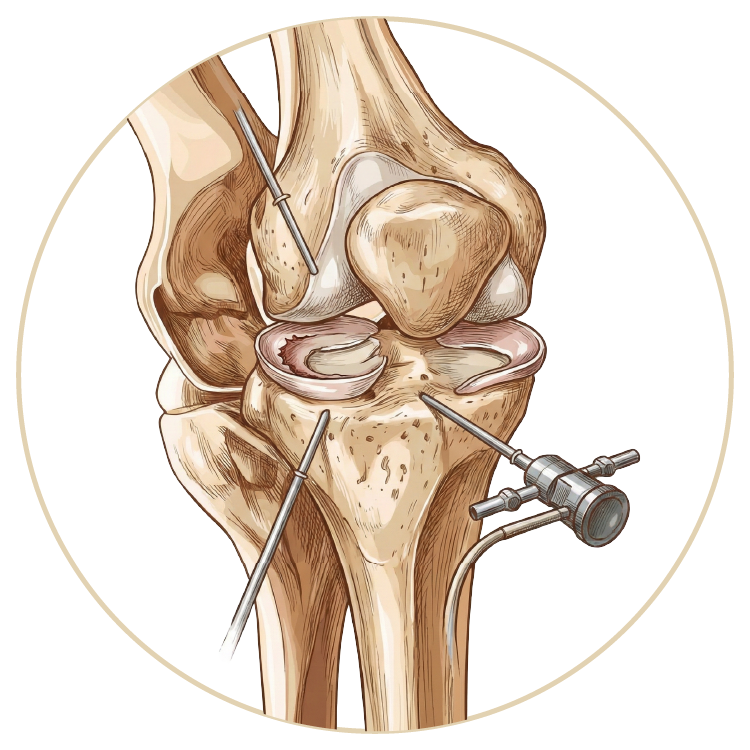

Diz Hastalıkları ve Tedavileri

Diz Hastalıkları ve Tedavileri

Ön Çapraz Bağ Ameliyatı

Menisküs Yırtığı

Menisküs Nakli

Kıkırdak Yaralanmaları

Diz Kireçlenme Tedavsi

Diz Artroskopisi